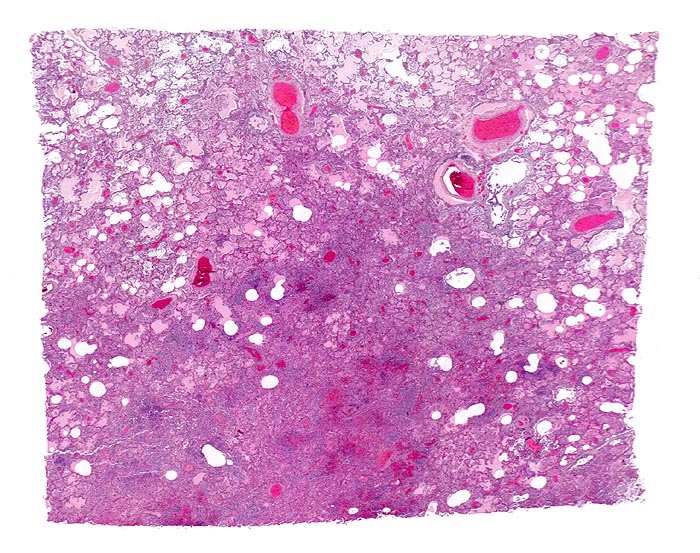

PathoPic – image database / PathoPic ID 4649 - Bronchopneumonie

Bronchopneumonie

Die Alveolen sind gefüllt mit rosafarbener Ödemflüssigkeit. Der unscharf begrenzte bläuliche Herd entspricht einem pneumonischen Infiltrat (Herdpneumonie) mit intraalveolärer Ansammlung neutrophiler Granulozyten.

Nach dem Verteilungsmuster der entzündlichen Infiltrate werden alveoläre und interstitielle Pneumonien unterschieden. Die alveolären Pneumonien werden unterteilt in die Lobärpneumonie und die Herdpneumonie. Ätiologische Pneumonie-Klassifikationen sind nur bedingt auf pathologisch-anatomische Befunde zu übertragen, da nur wenige Erreger charakteristische morphologische Veränderungen bewirken. Eine Lobärpneumonie tritt auf, wenn die Erreger die Alveolarräume so ausgedehnt und rasch befallen, daß sie erst vor anatomischen Grenzen (z.B. einem Lappenspalt) Halt machen.